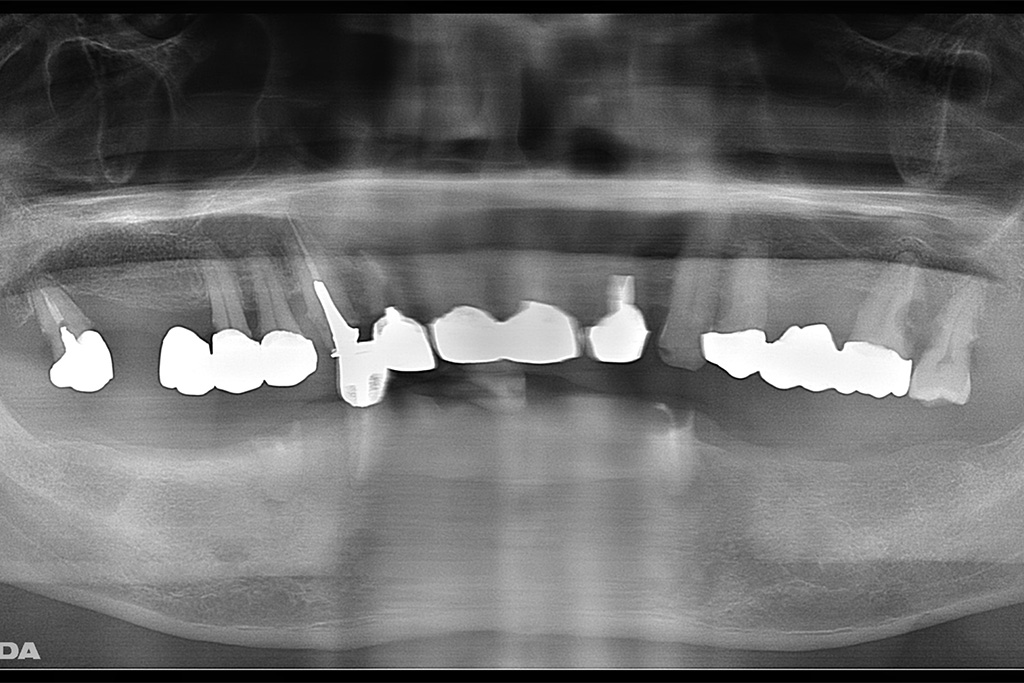

左側のレントゲンがが最初の状態です。右側がインプラントを入れ、被せ物まで入れた状態のレントゲンです。